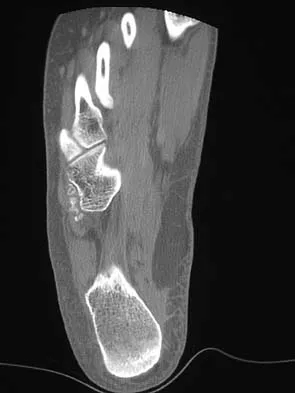

The oblique radiograph of the foot and the CT scan shown in Figures 10a and 10b show a patient whose symptoms have failed to respond to rest and non-steroidal anti-inflammatory drugs. What is the best course of action?